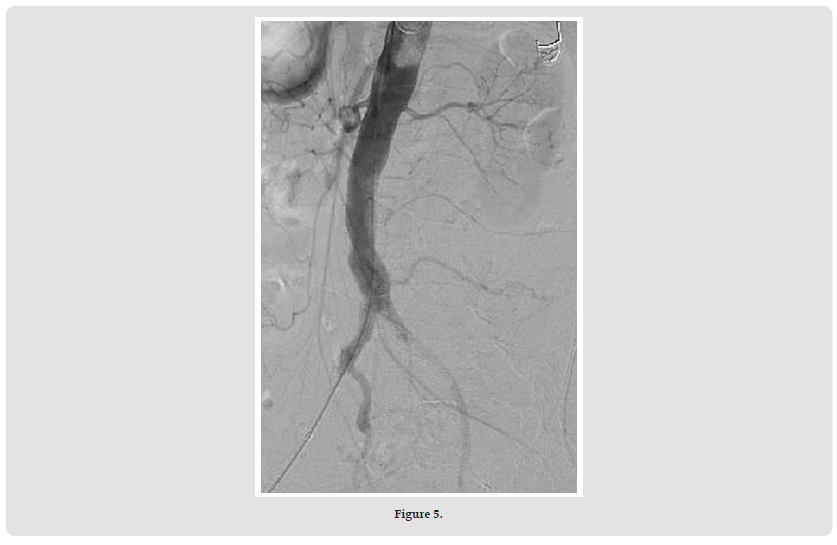

On the right side, the 18x38 mm BeGraft® Aortic Stent Graft (Bentley) was positioned halfway between the inferior mesenteric artery and the bifurcation, as planned (Figures 2 & 3). From both sides, a 10x37 mm BeGraft® Peripheral Stent Graft (Bentley) was deployed without predilatation into the iliac artery, positioned 10 mm up the aorta. After opening with a simultaneous kissing technique, angiography showed good results (Figure 4) and then the left side was stented with an 8x37 mm BeGraft® Peripheral Stent Graft (Bentley) with 10 mm overlap. The overlap was re-expanded with the 10 mm BeGraft® peripheral balloon. On control angiography, the inferior mesenteric artery and both internal iliac arteries remained open (the left side was also patent despite the preliminary CTA image) (Figure 5).